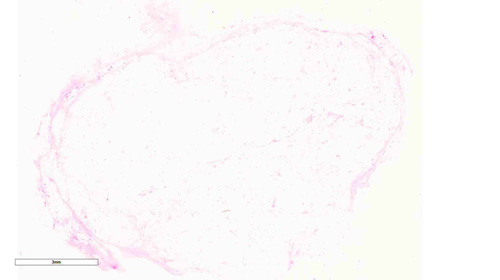

La otra variedad es el tejido adiposo pardo. A diferencia del amarillo, los adipocitos son pequeños y contienen múltiples vacuolas lipídicas en el citoplasma, siendo el núcleo central. Es más abundante en los animales hibernantes y animales recién nacidos. En adultos es vestigial, apreciándose en región axilar y en la cara ventral de la aorta predominantemente.

Busca el tejido adiposo pardo en la imagen